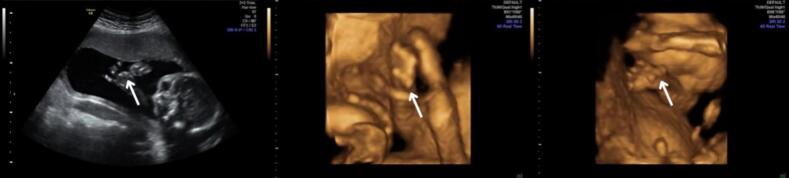

A curvature of a finger that bends inwards relative to the other fingers is a common observation during prenatal screening. When the angulation exceeds 10 degrees, it is known as “clinodactyly” and could suggest a variety of underlying issues. Even though it usually remains unnoticed during pregnancy, it may be a sign of serious fetal disease. We report the case of a fetus diagnosed with clinodactyly of the thumb accompanied by tachycardia, abnormal levels of maternal hormones in the first trimester and increased impedance to flow in the uterine arteries. Although non-invasive prenatal testing was normal, amniocentesis was carried out and two deviations at chromosome 20 were identified through molecular karyotyping. Our report aims to raise clinical suspicion regarding the potential association between genetic abnormalities and clinodactyly. A careful clinical and genetic consultation is required in order to achieve the most favorable outcome for both mother and child.